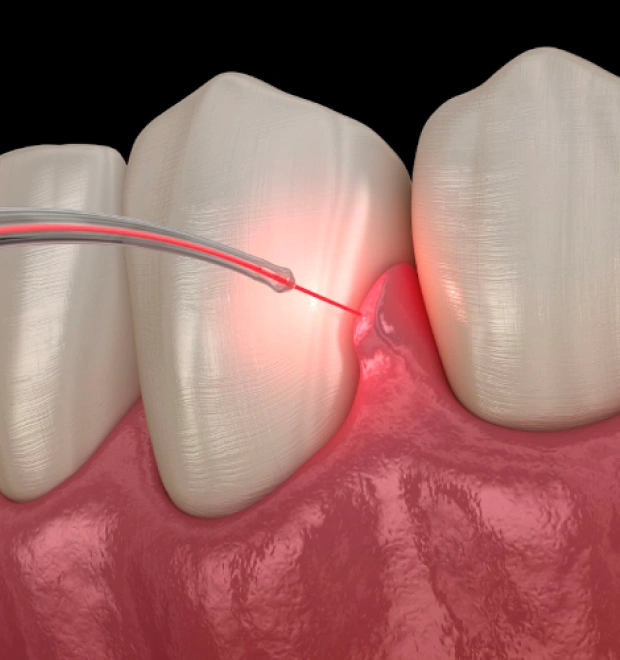

Laser frenum removal, also known as a frenectomy, is a minor surgical procedure used to remove or adjust the frenulum tissue that restricts movement in the mouth. The frenulum is a small band of tissue that connects areas such as the lips or tongue to the gums. When this tissue is too tight or short, it can interfere with normal functions like speaking, eating, or oral hygiene. At The Tooth, we perform laser frenectomy procedures using advanced technology for greater precision and comfort.

Laser treatment allows the procedure to be completed with minimal bleeding and faster healing compared to traditional surgical methods. Patients in Sacramento, Roseville, and Yuba City benefit from laser frenectomy because it provides a quick and effective solution for restricted oral movement.

Laser frenectomy is a quick and minimally invasive procedure that uses a specialized dental laser to gently remove or adjust the tight frenulum tissue.